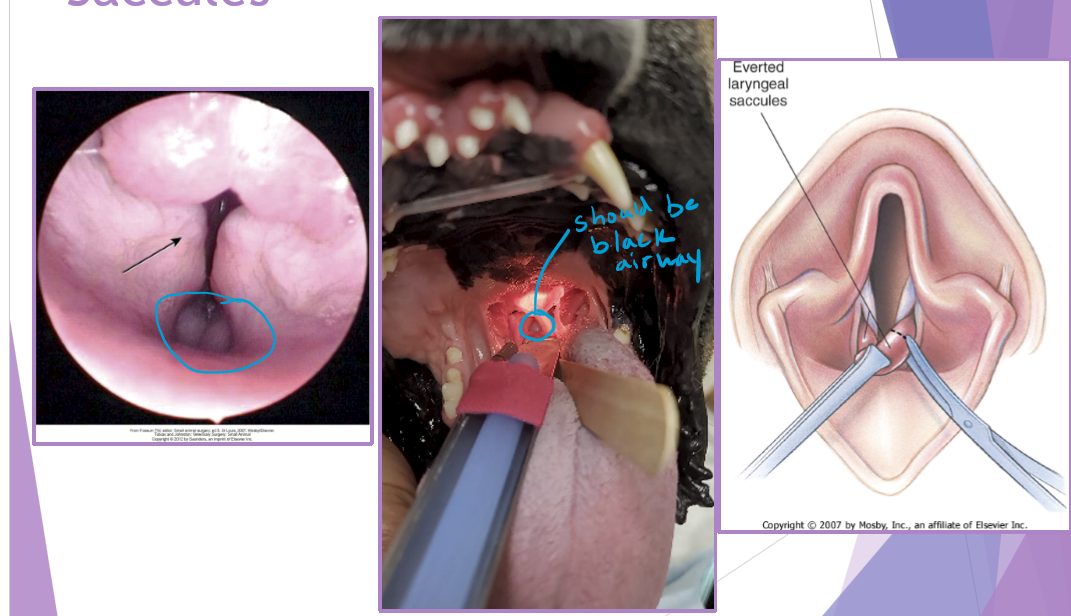

BOAS everted laryngeal saccules

prolapse of mucosa lining the laryngeal crypts

response to chronic high upper airway pressures

least common of the BAS complex

why a concern

further inhibit airflow, increases mucosal irritation

first stage of laryngeal collapse

surgical technique - cut them out but careful of vocal folds

extubate the patient temporarily

grasp and pull with forceps

resect saccule at its base with metzenbaum scissors

bleeding is controlled with direct pressure (from the ET tube)

happens due to chronic stress

laryngeal collapse: secondary due to chronic stress

due to chronic upper airway obstruction / airway resistance

3 stages

I - everted laryngeal saccules

II - I + collapsed cunieform cartilages (red)

III - I + II + collapsed corniculate cartilages (green) - everything collapsed down cant breath at all

treatment

laryngectomy

permanent tracheostomy